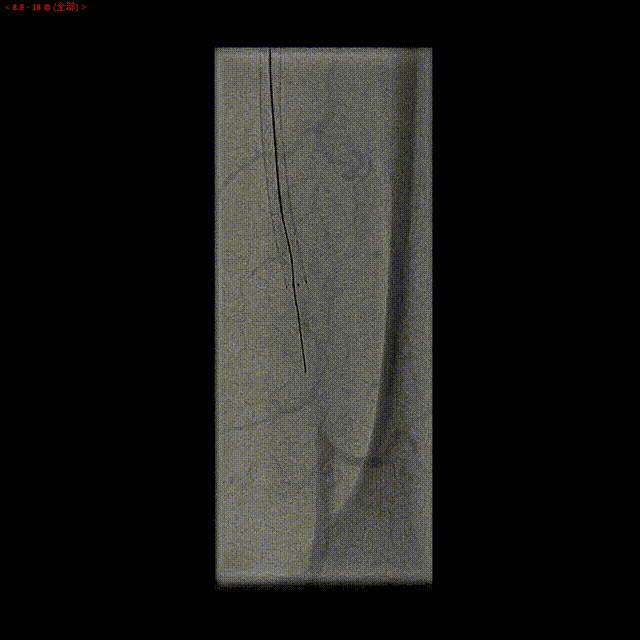

第二次激光后消蚀(能量60,频率60)

经激光消蚀后,通过导丝导管配合,逆向导丝轻松通过闭塞段。

逆向导丝到达股浅动脉近段,进入正向套鞘,导丝体外化,建立轨道。